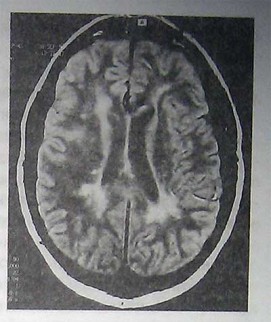

Внутричерепная гипотензия: КТ-исследования и их интерпретация